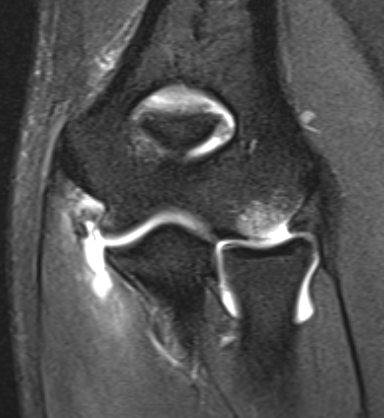

Acute full thickness UCL tear

UCLUCL

High grade partial distal UCL tear

PRLIPRLI